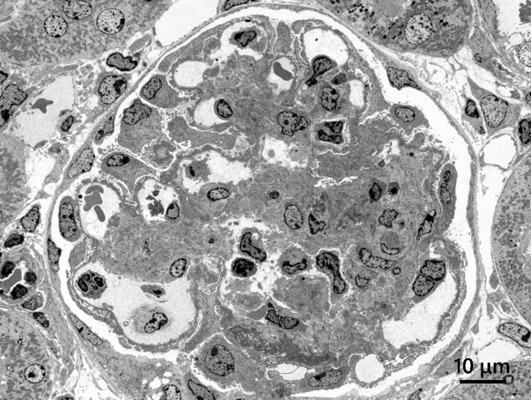

High-contrast observation

Specimen:Rat kidney

Accelerating voltage:80 kV, Magnification:x300